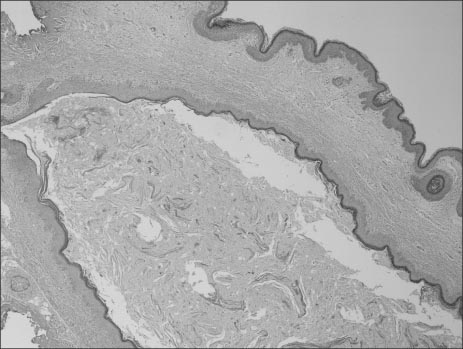

Fig. 4

Histopathologic finding reveals that the unilocular cystic cavity is lined by a stratified squamous epithelium (H&E, ×40).